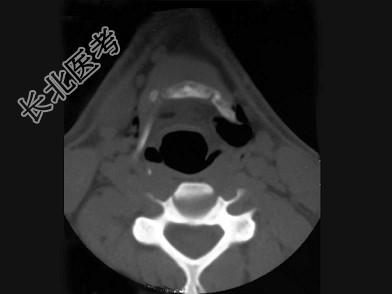

- 多项选择题男,27岁, 开车外出在高速行驶时翻车,呼吸困难, 喉部肿胀,CT检查如图所示, 正确的描述或诊断是 ( )

A、左侧甲状软骨骨折

B、左侧梨状窝软组织肿胀

C、颈部、胸骨下方软组织积气

D、左侧杓状软骨骨折

E、考虑喉、气管破裂